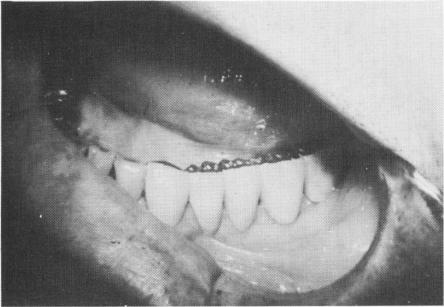

Fig. 11-38. The fixed partial denture ready for cementation.

Fig. 11-39. The bridge is cemented into position.

3 Fixed mandibular partial denture ready for cementation on bladevent